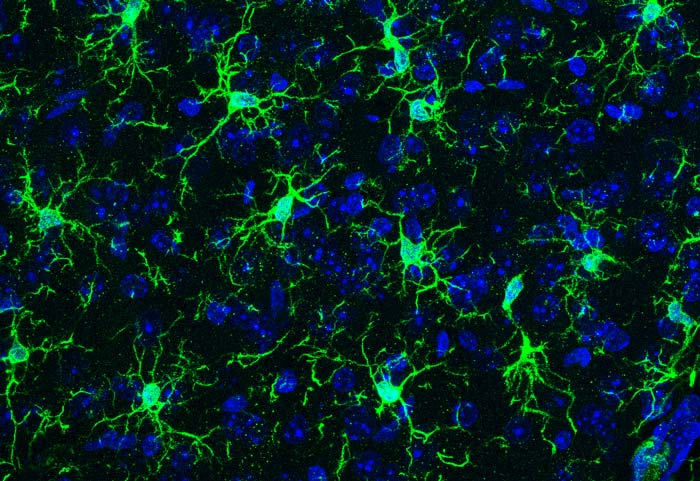

Les microglies sont des cellules immunitaires qui répondent à des traumatismes ou des signaux inflammatoires pour protéger le cerveau, agissant comme des senseurs capables de détecter de nombreux signaux environnementaux. Ces cellules immunitaires sont également impliquées dans différentes étapes du développement et du fonctionnement cérébral. Ainsi, des dysfonctionnements de ces cellules sont associés à un large spectre de pathologies humaines, allant des troubles neuro-développementaux jusqu’aux maladies neurodégénératives. Les microglies jouent donc un rôle crucial dans le fonctionnement normal et pathologique du cerveau, ce qui laisse suggérer qu’elles constituent une interface régulatrice entre les circuits cérébraux et l’environnement.

En combinant analyses génomiques globales et études histologiques, les chercheurs ont montré que les microglies sont profondément affectées par un dysfonctionnement du microbiote, dès les stades prénataux et ce, en fonction du sexe de l’animal : les microglies appartenant à des mâles semblent affectées au stade prénatal alors

que les microglies issues de femelles le sont à l’âge adulte. Ce surprenant dimorphisme sexuel fait écho au fait que l’occurrence de nombreuses pathologies neurodéveloppementales est plus élevée chez les hommes alors que les maladies auto-immunes sont plutôt prévalentes chez les femmes.